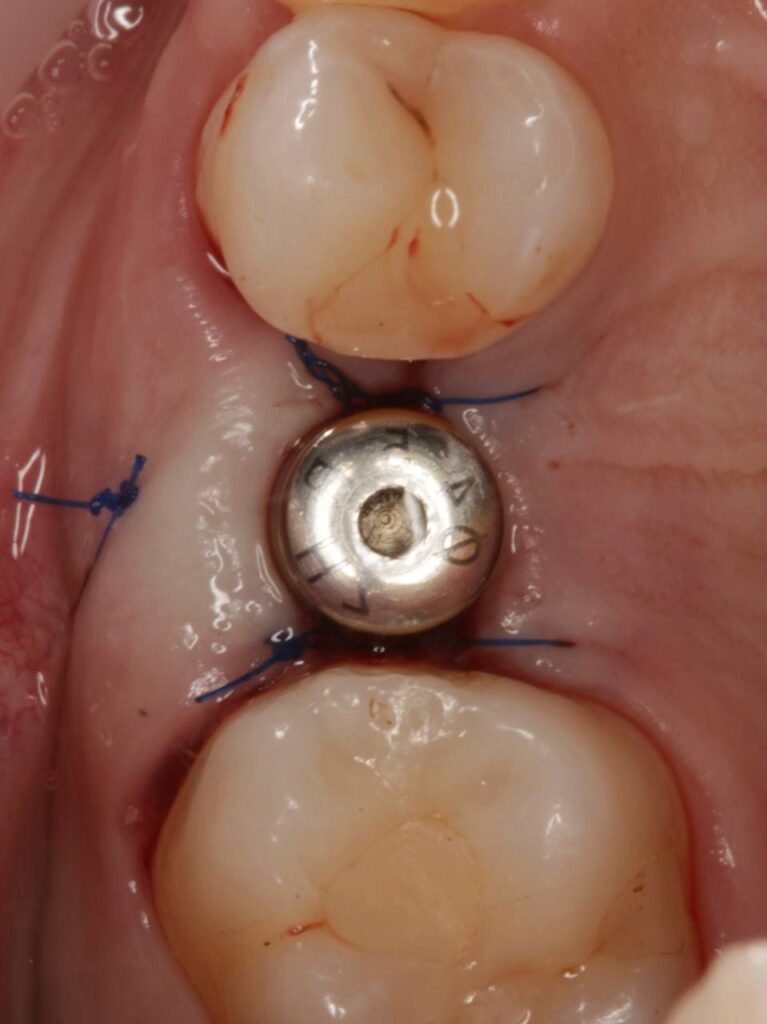

Специализация: терапия(эндодонтия), ортопедия, имплантология.